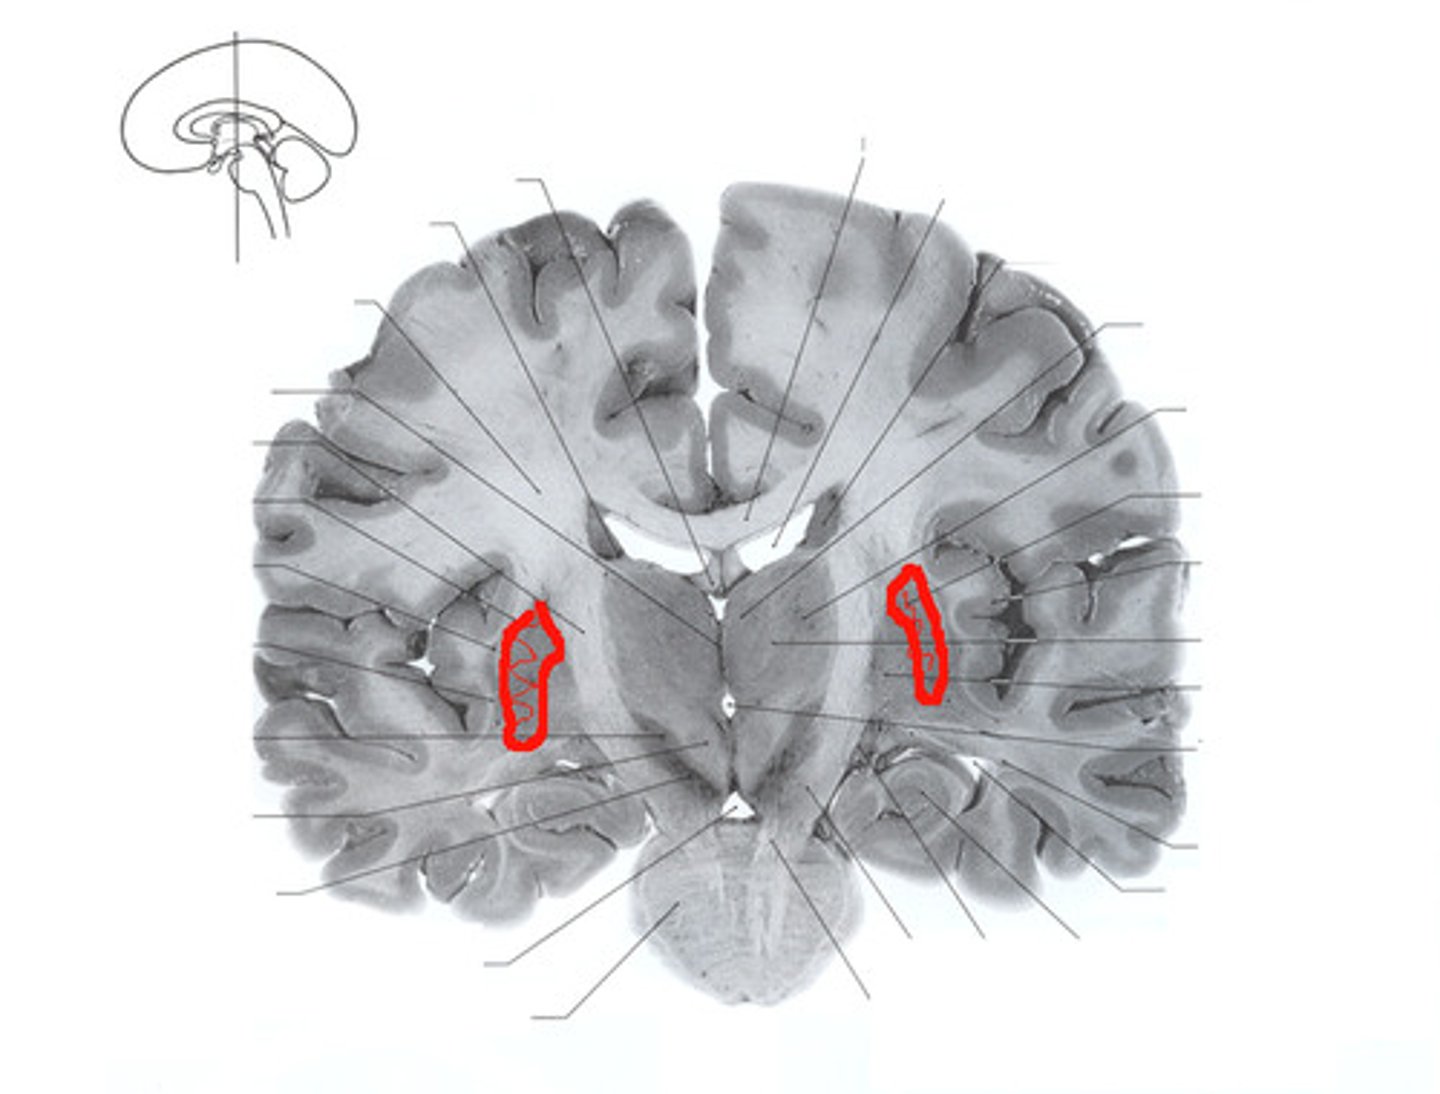

Caudate Nucleus

Globus Pallidus

Putamen

Choroid Plexus